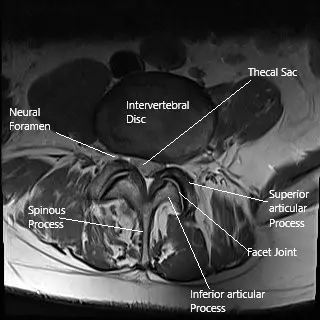

Laser spine surgery may be used to treat herniated intervertebral disc as seen on this axial MRI section of the lumbar spine.

The spine is made up of vertebrae separated by intervertebral discs. These discs act as cushions, allowing the spine to absorb shock and maintain flexibility. When a disc bulges or ruptures, it can press against the spinal cord or nerves, causing pain, weakness, and numbness. Laser spine surgery targets the problem area, typically a herniated disc, to relieve pressure on the nerves and alleviate the symptoms.